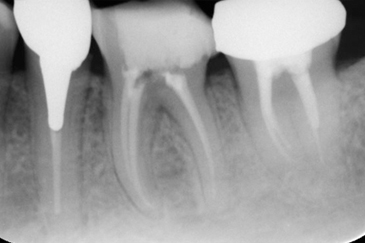

CASE 3

BEFORE

AFTER

基本情報

| 年齢・ 性別 |

40代・女性 |

|---|---|

| 主訴 | 歯が痛い・左上5 |

| 治療 内容 |

左上5・根管治療 (根管が曲がっている為細く曲がった歯の神経の治療に対応できる弾力が高く柔軟性 のあるニッケルチタンファイルを使用。 またラバーダムを用い防湿を行いながら治療 を進めました) |

| 治療 期間 |

2回 |

| 治療費 | 保険診療 約3,000円 |

| リスク・ 副作用 |

神経を取ってもすぐに痛みが引かない可能性があります。 神経の治療の刺激により、数日痛み・腫れがでる可能性があります。 細く繊細な器具を使用するため、器具が破折する可能性があります。 複雑な神経の治療では、大学病院もしくは専門医による治療が必要となることがあります。 または抜歯になることもあります。 |